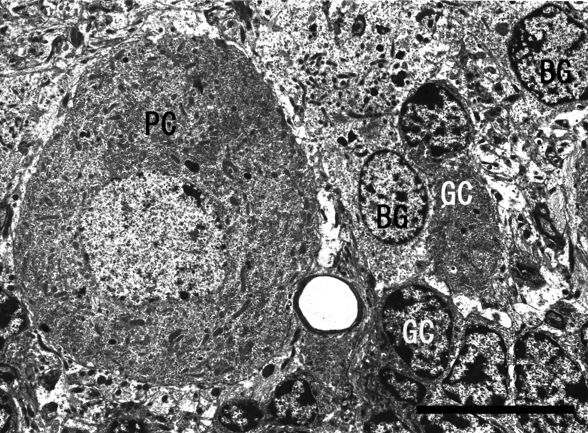

真核細胞

- 真核細胞には遺伝情報を封入する核があり、染色体にも配置されており、細胞小器官にも膜があります。 RNA の合成は核で行われ、タンパク質は細胞質のリボソームによって合成されます。 細胞核の概要、特徴、部分、機能については、こちらをご覧ください。

- この場合、微小管で構成される非常に高度な細胞骨格があり、微小管が持つさまざまな細胞小器官をサポートし、細胞の機能を実行します。ここでは、 細胞骨格とは何か、特徴、機能、構造など、細胞骨格について詳しく学ぶことができます。

- 最も特徴的なのはミトコンドリアで、ここで呼吸が行われ、その結果としてエネルギー生成が行われます。このリンクでは、ミトコンドリアの概要: 機能と構造が表示されます。

- また、タンパク質合成のためのリボソームを含む 粗面小胞体と、脂質を合成して細胞毒素を除去する平滑小胞体も備えています。

- ゴルジ装置は、他の細胞小器官から受け取った生成物を処理および輸送して、細胞内またはその表面ですぐに使用できる小胞を作成します。ここで、ゴルジ装置の詳細を読むことができます: 定義と機能。

- 細胞には、分子を処理する酵素を備えたリソソームがあります。ペルオキシソームも似ていますが、酸化によって生じる過酸化水素の分解に特異的です。このリンクでは、リソソームの定義、特性、機能について詳しく説明します。